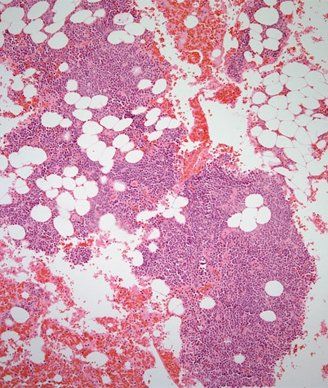

Multiple myeloma showing sheets of tumor cells admixed with adipose tissue